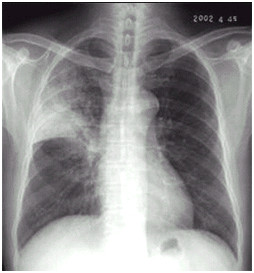

02卷-4.男性,24岁,发热、咳嗽、咳痰4天。诊断(本题满分2.00分)

A.右上肺不张

B.右上胸膜肥厚

C.右上肺癌

D.右上肺炎

本题答案:D

题目解析:

【该题针对“ X线-肺癌 ”知识点进行考核】